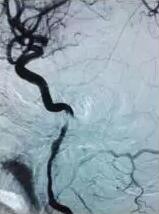

根據(jù)尹先生的病情,張主任先對(duì)其進(jìn)行了藥物治療,積極完善腦血管造影,確診尹先生腦梗死是由于頸動(dòng)脈栓子形成及脫落引起,同時(shí)頸動(dòng)脈夾層導(dǎo)致重度血管狹窄,如果繼續(xù)撕裂或破裂,隨時(shí)會(huì)有生命危險(xiǎn)。經(jīng)過(guò)病情討論后,張主任決定采用“頸動(dòng)脈支架植入+血管成形”,覆蓋夾層,改善狹窄血管。手術(shù)歷時(shí)1個(gè)多小時(shí),并取得成功,治療非常滿(mǎn)意。二十天后,坐著輪椅來(lái)的尹先生,健步走出了醫(yī)院,語(yǔ)言功能、肢體偏癱等均恢復(fù)正常。

前與術(shù)后圖片對(duì)比(左圖術(shù)前  右圖術(shù)后)